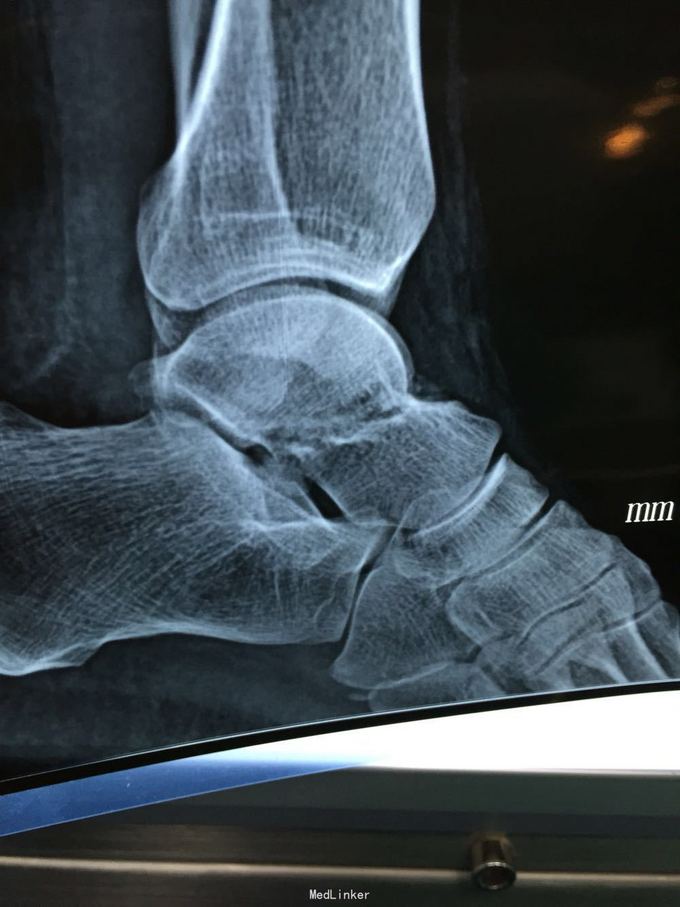

距骨骨折

患者因车祸致左足疼痛1小时入院

左足背肿胀明显,压痛

左距骨骨折